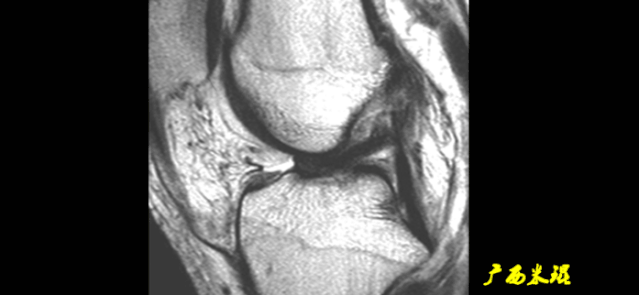

6)假瘤:

-

韧带损伤后断端较整齐,残端组织增生并被滑膜包裹呈“瘤状”,如果突出于前方为“独眼征”。

多见于韧带股骨附着部撕裂及部分撕裂。